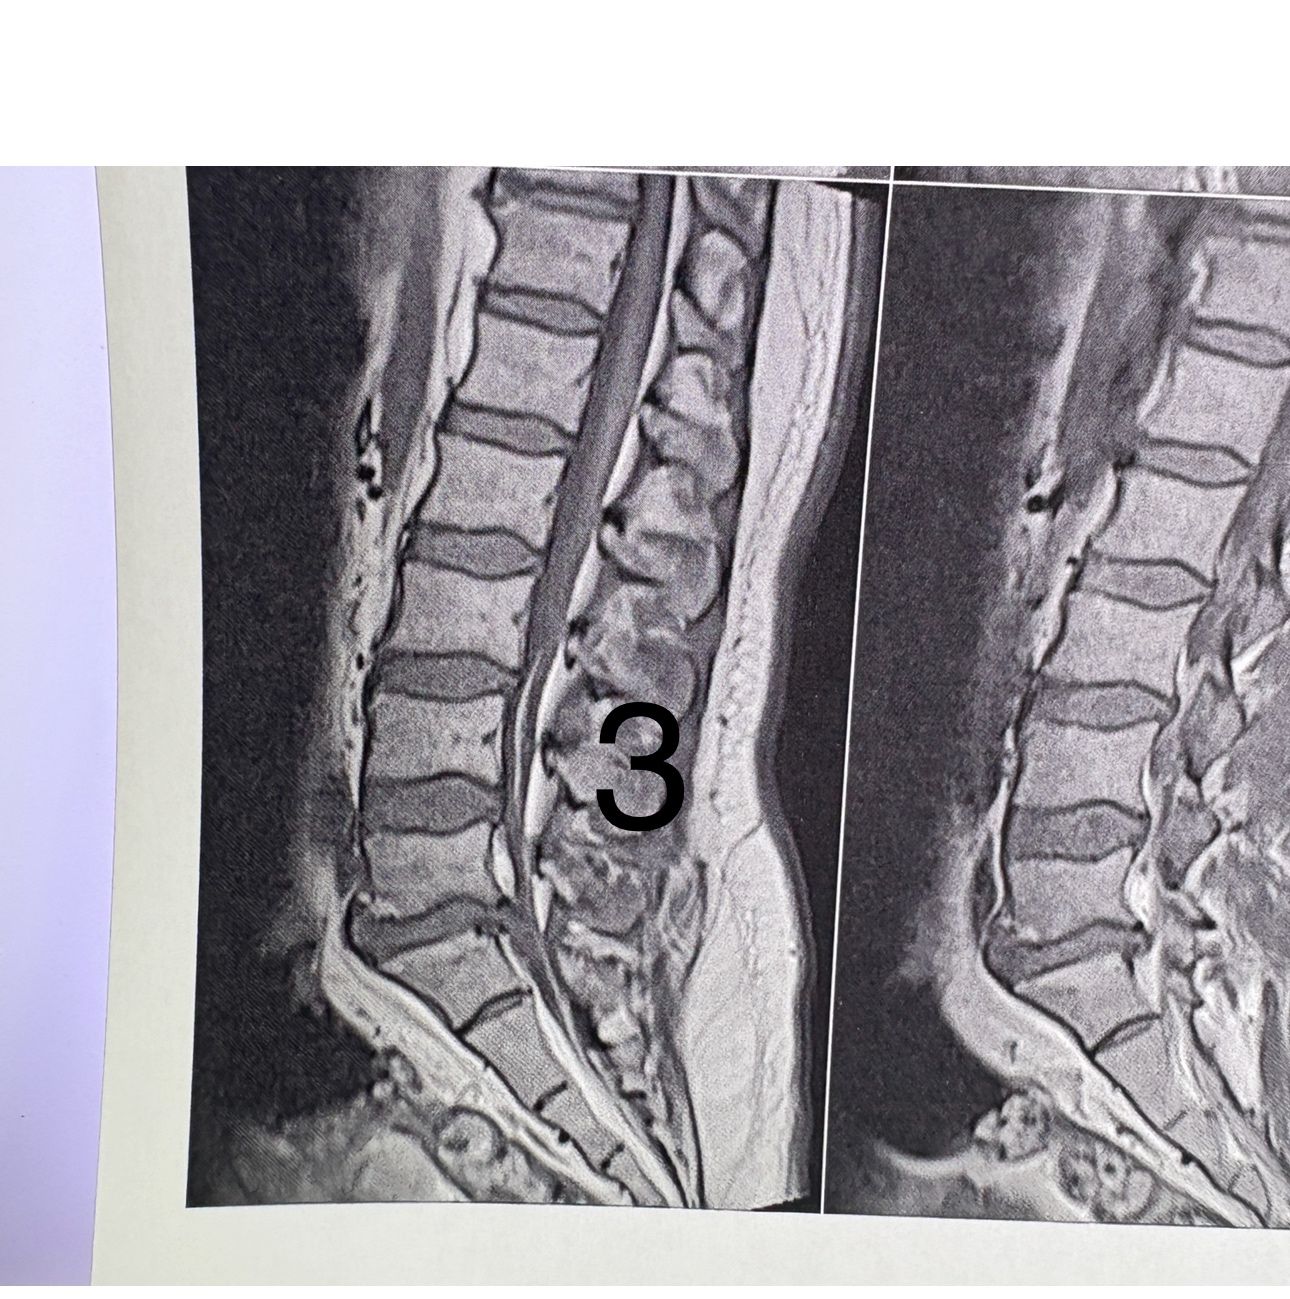

32 years female patient presented to my office one year ago with moderate cervical pain and R. Arm pain ,mild LBP with no radicular pain. Her mri in C/s had few bulges and few segmentsl dysfunctions

Her lumbar mri showed Contained R. Para. L5-S1 extrusion

She got treatment just for her neck and exercises for her low back. Few months later had lumbar disc surgery

Few days ago on may on june 08/2025, presented with severe LBP and no radicular pain

I have post her lumbar MRI before and after surgery. I consulted with a neurosurgeon at our clinic and he said doesn’t need another surgery because doesn’t have radicular pain or neurological deficits

For her pain i have started to do mild decompression by Cox and DTS and acupuncture, no adjustment whatsoever.

Please mention what differences you see before and after surgery